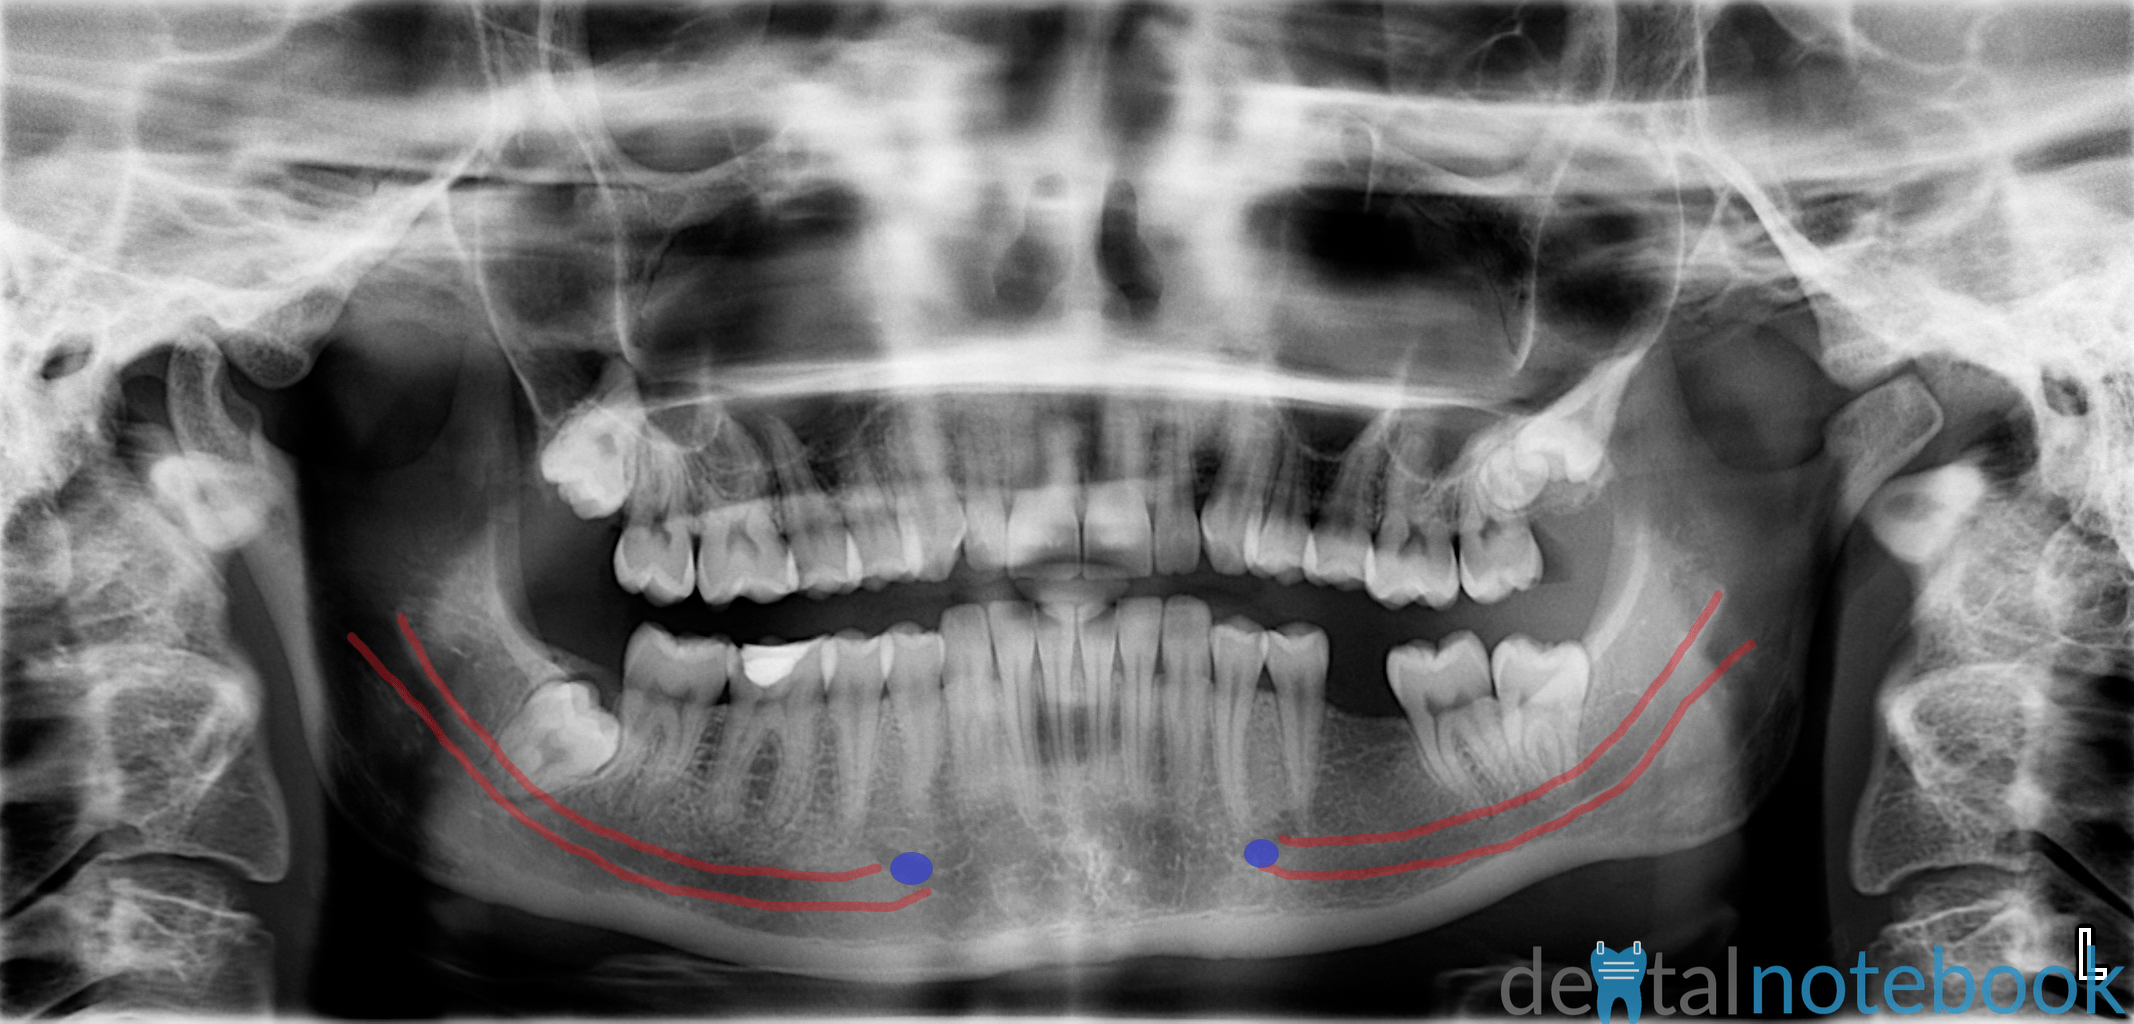

Automatic segmentation of mandible in panoramic xray PMC Anatomical Landmarks Panoramic This is an online quiz called anatomical landmarks (panoramic) you can use it as anatomical landmarks (panoramic) practice, completely free to play. Select a case to begin: There is a printable worksheet. Review of normal anatomical landmarks and variations. Panoanatomy is designed to help you practice anatomic landmark recognition on panoramic radiographs. It is important to understand the landmarks normally. Anatomical Landmarks Panoramic.